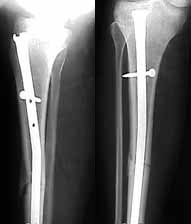

The patient came to me two days after injury. Her general condition was not good with Hb 6.7 gm%. After Blood transfusions in the first stage I did standard femoral Interlocking - 10mm nail with two proximal screws. 3 days later I did Tibial and Humeral Interlocking nailing - 8mm and 6mm nail respectively with proximal locking only.

On discharge 10 days later she wass walking independently with Zimmer frame with full knee hip and shoulder movements. Xrays are attached.